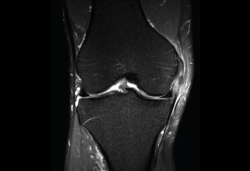

Figura 53. Corte de secuencia sagital (A) y axial (B) T2 Fat-Sat de RM de rodilla: lesiones osteocondrales en el fémur y la rótula.